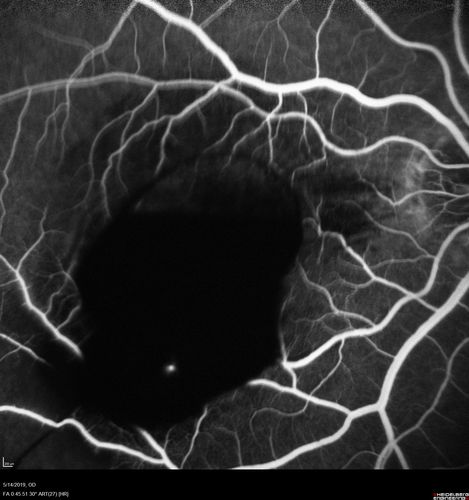

Macroaneurysm - Macular Hemorrhage - Branch Retinal Aterial Occlusion

62 year old African American female with chronic hypertension and vision loss for 2 weeks. VA is 20/400

Macroaneurym - Fresh Macular Hemorrhage - branch retinal arterial occulsion distal to MA